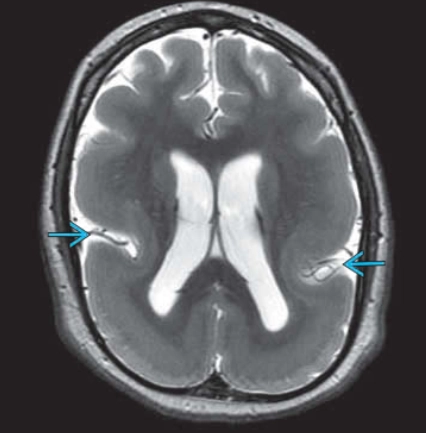

• Nứt não (Schizencephaly)

• To một bên bán cầu não (Hemimegalencephaly - HMEG)